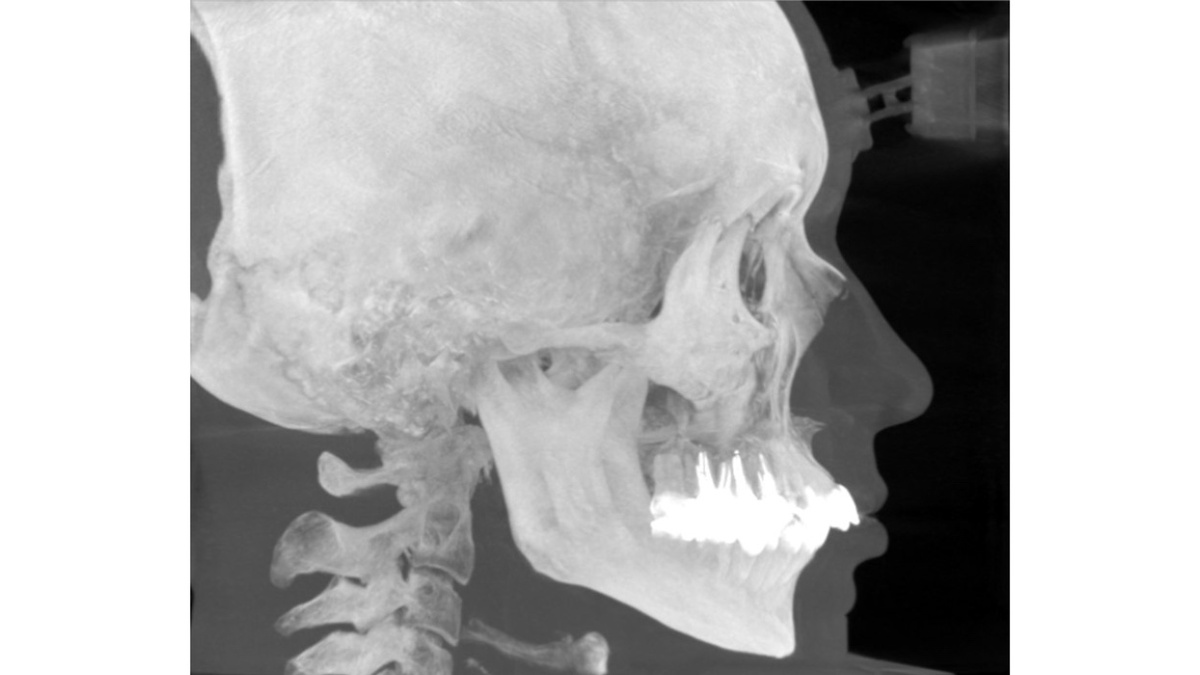

Ортодонты всегда отличались применением рентген-диагностических методов от стоматологов других специальностей. Например, одним из специфических методов остается телерентгенография в боковой и прямой проекциях. С развитием трехмерной рентген-диагностики часть этих особенностей перешла и в тонкости выполнения компьютерной томографии.

В этой статье стоматолог-рентгенолог Александр Потапов рассказал про основные особенности диагностики, важные нюансы позиционирования пациента и ошибки, которые могут повлиять на точность анализа.

Достаточный объем сканирования

Первая особенность - большое поле сканирования. В него должны входить следующие анатомические структуры:

• турецкое седло (Se)

• носо-лобный шов (N)

• скуло-лобные швы (FZP)

• наружные слуховые проходы (Po)

• подбородок (Me)

• шейные позвонки (до 4-5-го)

• подъязычная кость

• профиль мягких тканей

Чтобы все перечисленные структуры попадали в исследование, высота цилиндра сканирования должна составлять не менее 15 см. При меньшей высоте возрастает риск выпадения части структур из зоны видимости.

Оптимальный диаметр цилиндра для захвата обоих ушных проходов и кончика носа - не менее 16–17 см, а идеальным считается показатель около 20 см.